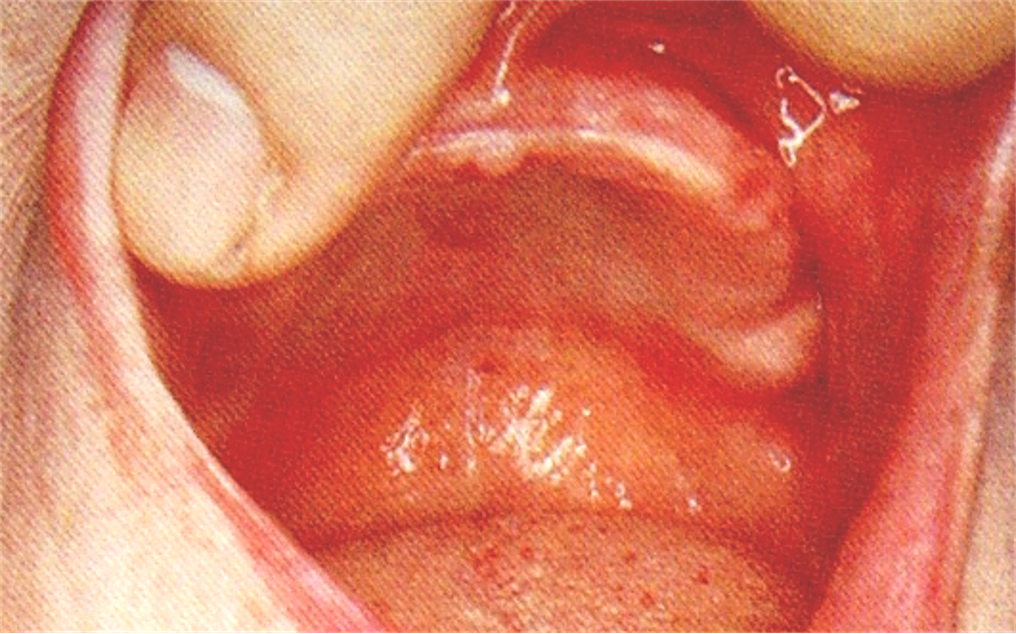

6.磨牙后垫(retromolar pad)

位于下颌最后磨牙牙槽嵴远端的粘膜软垫,覆盖在磨牙后三角上,由疏松的结缔组织构成,含黏液腺。

磨牙后垫的形态和位置比较稳定,作为排人工牙时的解剖标志;垂直向:下颌第一磨牙的颌平面与磨牙后垫的1/2处等高;

前后向:下颌第二磨牙应位于磨牙后垫前缘;

颊舌向:磨牙后垫颊面、舌面向前与下颌尖牙的近中面形成一个三角形。